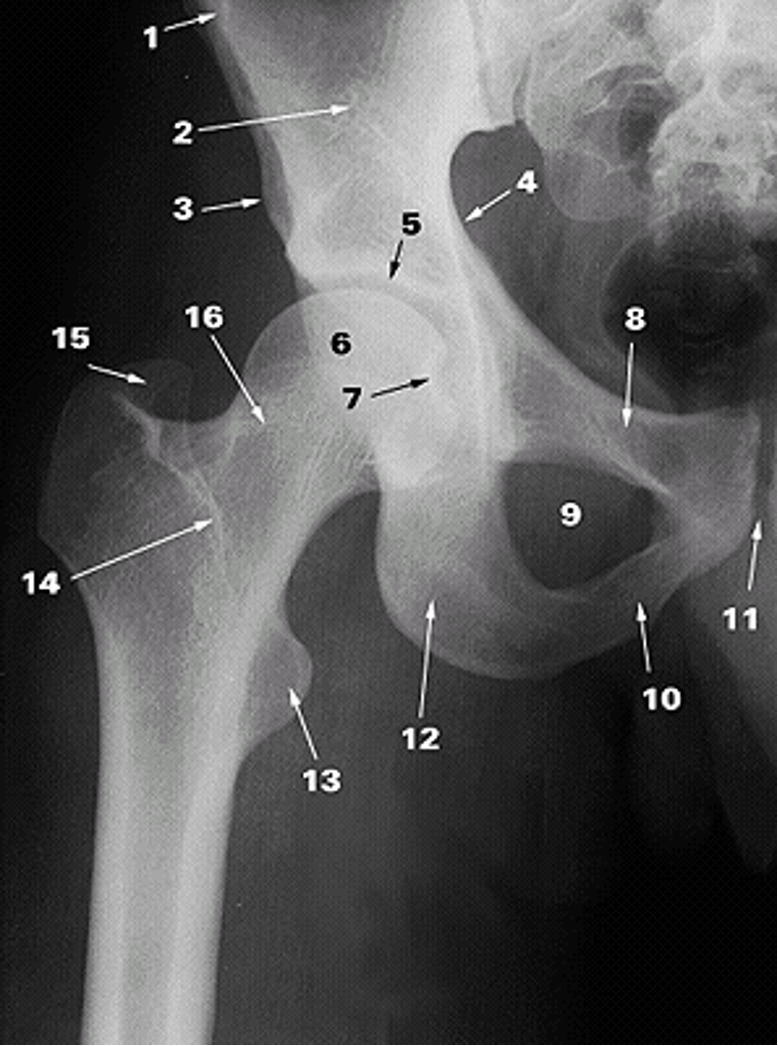

<p>1.</p>

1.

Anterior Superior Iliac Spine (2)

New cards

<p>2.</p>

2.

Ilium (2)

<p>3.</p>

3.

Anterior Inferior Iliac Spine (2)

<p>4.</p>

4.

Pelvic Brim

<p>5.</p>

5.

Acetabular Fossa (2)

<p>6.</p>

6.

Head of Femur (2)

<p>7.</p>

7.

Fovea

<p>8.</p>

8.

Superior Ramus of Pubis (2)

<p>9.</p>

9.

Obturator Foramen (2)

<p>10.</p>

10.

Inferior Ramus of Pubis (2)

<p>11.</p>

11.

Pubic Symphysis (2)

<p>12.</p>

12.

Ischium

<p>13.</p>

13.

Lesser Trochanter (2)

<p>14.</p>

14.

Intertrochanteric Crest (2)

<p>15.</p>

15.

Greater Trochanter (2)

38

<p>16.</p>

16.

Neck of Femur (2)